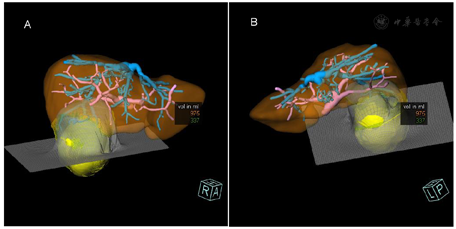

三维容积分析RECIST肝脏总容积1311.68ml,左叶体积约374.8ml,右叶体积约936.81ml;病灶直径76.28mm,最大正交直径74.63mm,容积243.31ml,虚拟手术2cm安全距离内容积约:337ml(虚拟手术切除容积),2cm安全距离外容积约:975ml(虚拟手术剩余肝容积)。

我国肝癌发病率高,呈逐年上升的趋势,病死率居恶性肿瘤第二位[1]。肝切除术是肝癌最主要的治疗手段。精细的术前评估和合理的手术规划,在保证彻底切除肿瘤的同时尽可能保存残余肝脏体积和功能,可以减少手术并发症,延长患者生存期。肝脏肿瘤三维可视化是指用于显示、描述和解释肝脏肿瘤三维解剖和形态特征的一种影像学工具。以SOMATOM Definition Flash机器采集的原始数据为基础,采用三维可视化软件重建的图像,可单独或联合显示肿瘤、全肝、肝动脉、肝静脉及门静脉的解剖关系及变异情况,确定拟切除的肝脏范围及受累需要重建的血管,对肿瘤体积及剩余肝脏体积进行精准定量,指导临床医生选择合适的手术方式,提高手术的精准性和安全性[2]。图像立体直观,且符合个性化需求,并可永久性存储重建后的图像,对手术方式的选择及术后随访有重要意义。